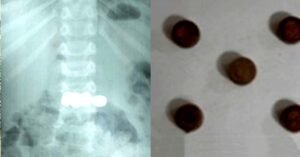

കളിപ്പാട്ടത്തിൽ നിന്നെടുത്ത അഞ്ച് കോയിൻ ടൈപ്പ് ബാറ്ററികൾ വിഴുങ്ങി രണ്ടുവയസുകാരൻ വയനാട്: മേപ്പാടിയിൽ കളിപ്പാട്ടത്തിൽ നിന്നെടുത്ത അഞ്ച് കോയിൻ ടൈപ്പ് ബാറ്ററികൾ വിഴുങ്ങിയ രണ്ട് വയസ്സുകാരനെ സമയബന്ധിതമായ ചികിത്സയിലൂടെ രക്ഷപ്പെടുത്തി. വലിയ ആശങ്ക സൃഷ്ടിച്ച സംഭവത്തിൽ എൻഡോസ്കോപ്പി വഴി ബാറ്ററികൾ വിജയകരമായി പുറത്തെടുത്തതോടെ കുട്ടി അപകടനില തരണം ചെയ്തു. ബത്തേരി മൂലങ്കാവ് സ്വദേശികളായ ദമ്പതികളുടെ മകനാണ് വീട്ടിൽ കളിക്കുന്നതിനിടെ ബാറ്ററികൾ വായിൽ ഇട്ടത്. കളിപ്പാട്ടത്തിൽ ഉണ്ടായിരുന്ന ചെറിയ കോയിൻ ബാറ്ററികളാണ് കുട്ടി വിഴുങ്ങിയത്. സംഭവം വീട്ടുകാർ ഉടൻ … Continue reading കളിപ്പാട്ടത്തിൽ നിന്നെടുത്ത അഞ്ച് കോയിൻ ടൈപ്പ് ബാറ്ററികൾ വിഴുങ്ങി രണ്ടുവയസുകാരൻ; ഡോക്ടർമാർ പുറത്തെടുത്തത് ഇങ്ങനെ: